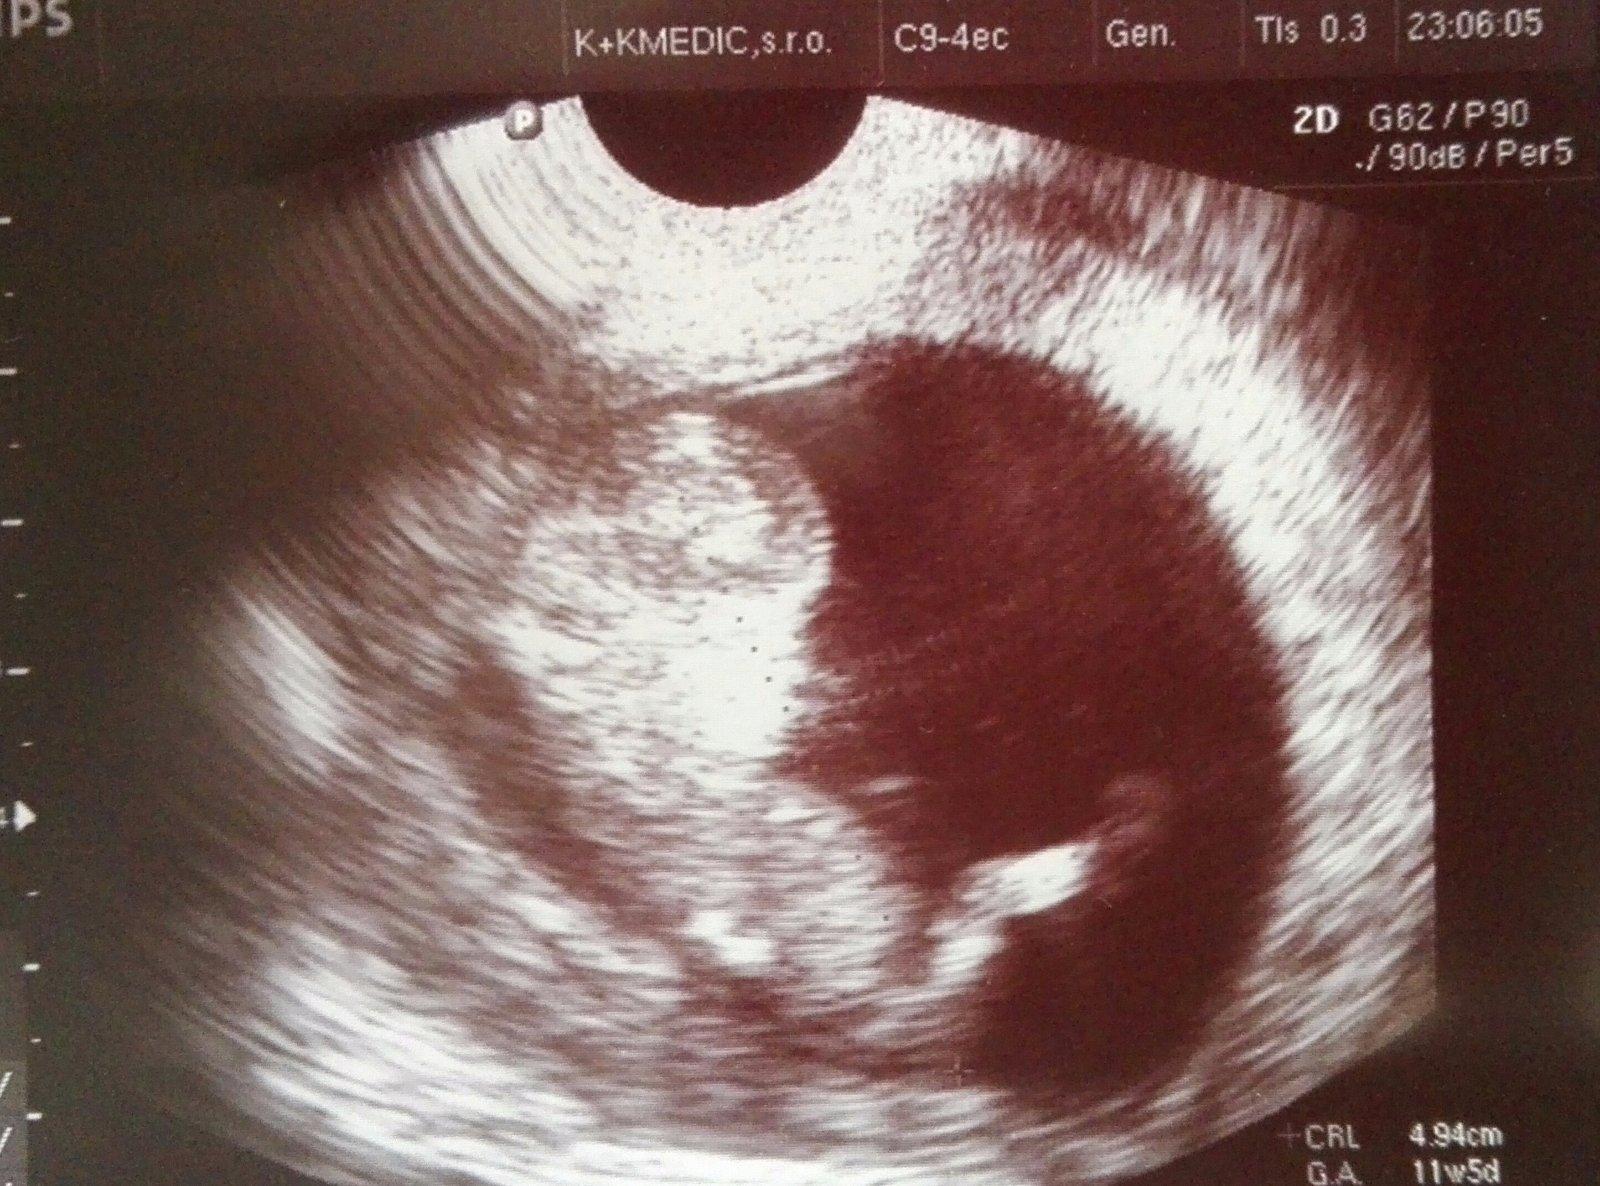

Pridajte sem do témy fotku Vášho dieťatka, ktorú máte najradšej, na ktorú máte pekné spomienky a napíšte nám krátky príbeh prečo práve táto fotka je Vám najmilšia.